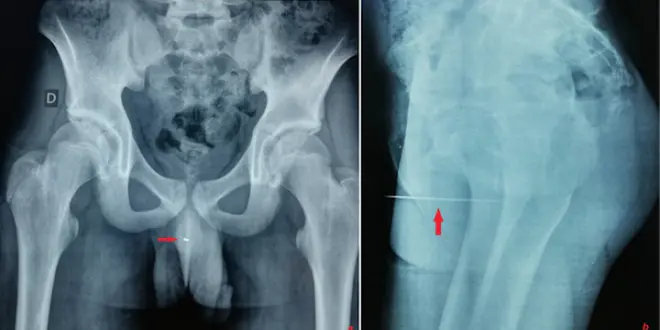

Les médecins de l’hôpital tunisien de La Rabta n’en ont pas cru leurs yeux. Comme ils l’indiquent dans un papier publié dans le numéro de juillet de la revue Urology Case Reports, ils ont retrouvé une aiguille dans le pénis d’un patient. Et pas n’importe laquelle : une tige en métal de 9 cm, logée à 5 cm de profondeur dans l’urètre. L’adolescent de 14 ans a indiqué avoir enfoncé l’aiguille pour la stimulation érotique que cela lui procurait.

Selon les auteurs de l’article, des cas comme celui-ci sont "très rares", et les patients, trop honteux, consultent souvent tardivement. Leur patient a pour sa part été placé sous anesthésie générale, avant que les médecins ne lui retirent l’aiguille de l’urètre au forceps.

© Urology Case Reports